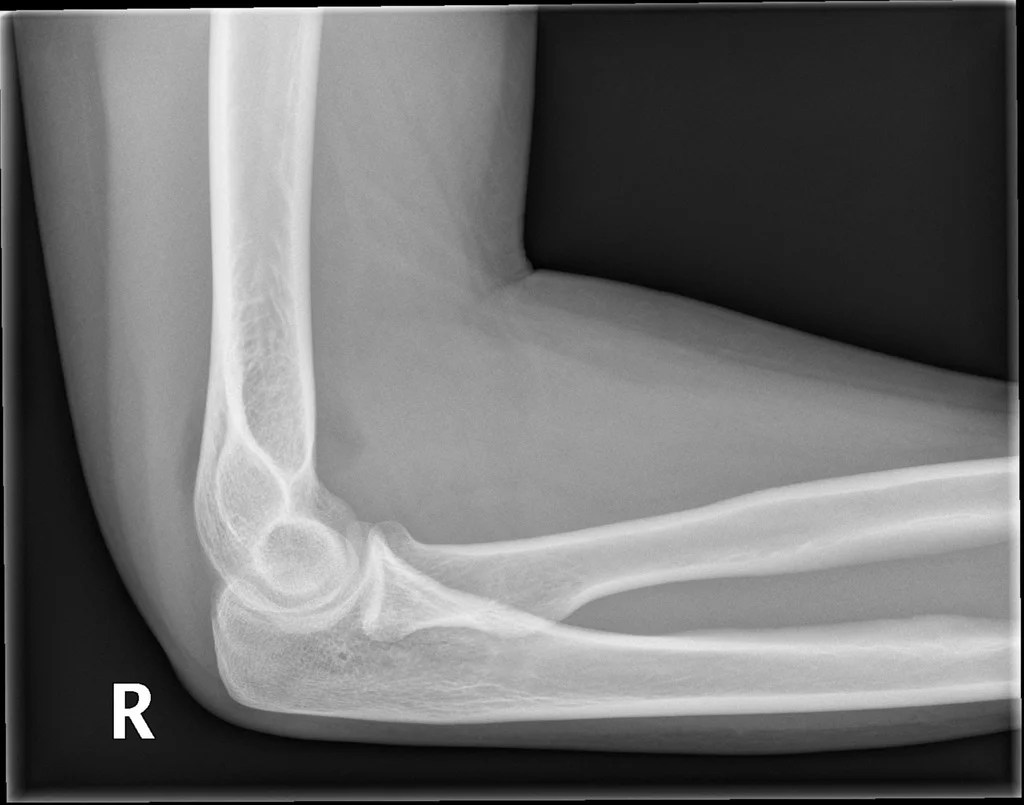

Elbow joint effusion (sail sign) Image

Elbow joint effusion (sail sign) Image What Is Joint Effusion In The Elbow Joint effusion tends to affect larger joints such as the. On a lateral radiograph, effusion causes displacement. Elbow joint effusion is a swelling of the elbow joint from fluid buildup. The sail sign is the key to recognizing an elbow joint effusion. In adults, the occult fracture is most commonly of the radial. An elbow joint effusion in the setting. What Is Joint Effusion In The Elbow.